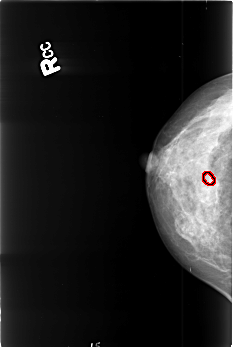

Digital Database for Screening Mammography

Volume: benign_06 Case: B-3419-1

B_3419_1.RIGHT_CC

RIGHT_CC LINES 4504 PIXELS_PER_LINE 3024 BITS_PER_PIXEL 12 RESOLUTION 50 OVERLAY

FILE: B_3419_1.RIGHT_CC.OVERLAY

TOTAL_ABNORMALITIES 1

ABNORMALITY 1

LESION_TYPE CALCIFICATION TYPE PLEOMORPHIC DISTRIBUTION CLUSTERED

ASSESSMENT 4

SUBTLETY 3

PATHOLOGY BENIGN

TOTAL_OUTLINES 1